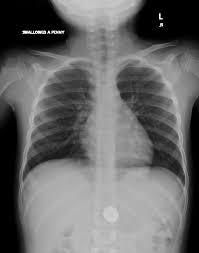

Your doctor may perform an X-ray to locate the item. Or a bronchoscopy to take a closer look at the airways if the person can’t breathe easily. A bronchoscopy is a procedure where a doctor uses a thin tube with a camera to look at the airways. This camera is a bronchoscope. Doctors also take other symptoms into account when making a diagnosis. You may need to provide a list of signs that led you to suspect a foreign object was swallowed.